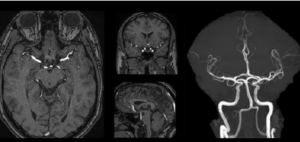

The DAISI project focuses on the development of an artificial intelligence solution integrated into the workflow to assist in the detection, orientation and follow-up of unruptured intracranial aneurysms on MRI. Intracranial aneurysm is a not rare arterial pathology (3%), asymptomatic except for complications, and difficult to diagnose on cerebral MRI performed for another indication.

Through the development of innovative Deep Learning algorithms, DAISI will standardize, accelerate and secure vascular analysis in MRI and thus the early identification of patients with aneurysms. A real public health issue, the target is to reduce by 90% the rate of under-diagnosis of the pathology, which means an impact on several thousand patients per year in France.

Intracranial Aneurysm